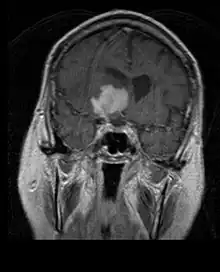

La tomodensitométrie (TDM) et L'imagerie par résonance magnétique (IRM) peuvent détecter efficacement une néoplasie dans le cerveau. L'IRM est plus sensible que la TDM pour identifier les lésions, mais présente des contre- indications pour les patients porteurs de stimulateurs cardiaques, de prothèses incompatibles, de clips métalliques et contre-indications. La TDM reste la méthode de choix pour détecter les calcifications au sein des lésions ou les érosions osseuses de la calotte ou de base du crâne. L'utilisation d' agents de contraste, iodés dans le cas du scanner et paramagnétiques (gadolinium) dans le cas de l'IRM, permet l'acquisition d'informations sur la vascularisation et l'intégrité de la barrière hémato-encéphalique, une meilleure définition de la tumeur tumorale par rapport à l' œdème environnant et à la génération d' hypothèses sur le degré de malignité. L'examen radiologique permet également d'évaluer les effets mécaniques et les modifications importantes des structures cérébrales résultant de la tumeur, telles que l' hydrocéphalie et les hernies, dont les effets peuvent être fatals. Enfin, en préparation à la chirurgie, ce diagnostic peut être utilisé pour déterminer la localisation de la lésion ou l'infiltration de la tumeur dans des zones vitales du cerveau. À cette fin, l'IRM est plus efficace que la tomodensitométrie car elle peut fournir des images en trois dimensions.

Sur-L'IRM montre une tumeur intracrânienne comme une lésion massive qui peut devenir plus luminescente après utilisation du produit de contraste. Cependant, il y a toujours une anomalie de signal dans -L'imagerie par résonance magnétique, qui indique la présence d'une néoplasie ou d'un œdème vasogénique. Habituellement, une luminescence accrue (amélioration du contraste) indique une tumeur d'un grade supérieur de malignité. Un anneau de contraste est caractéristique du glioblastome, avec la partie luminescente correspondant à la partie vitale de la tumeur maligne, et la plus foncée - zone hypointense correspondant à une nécrose tissulaire.